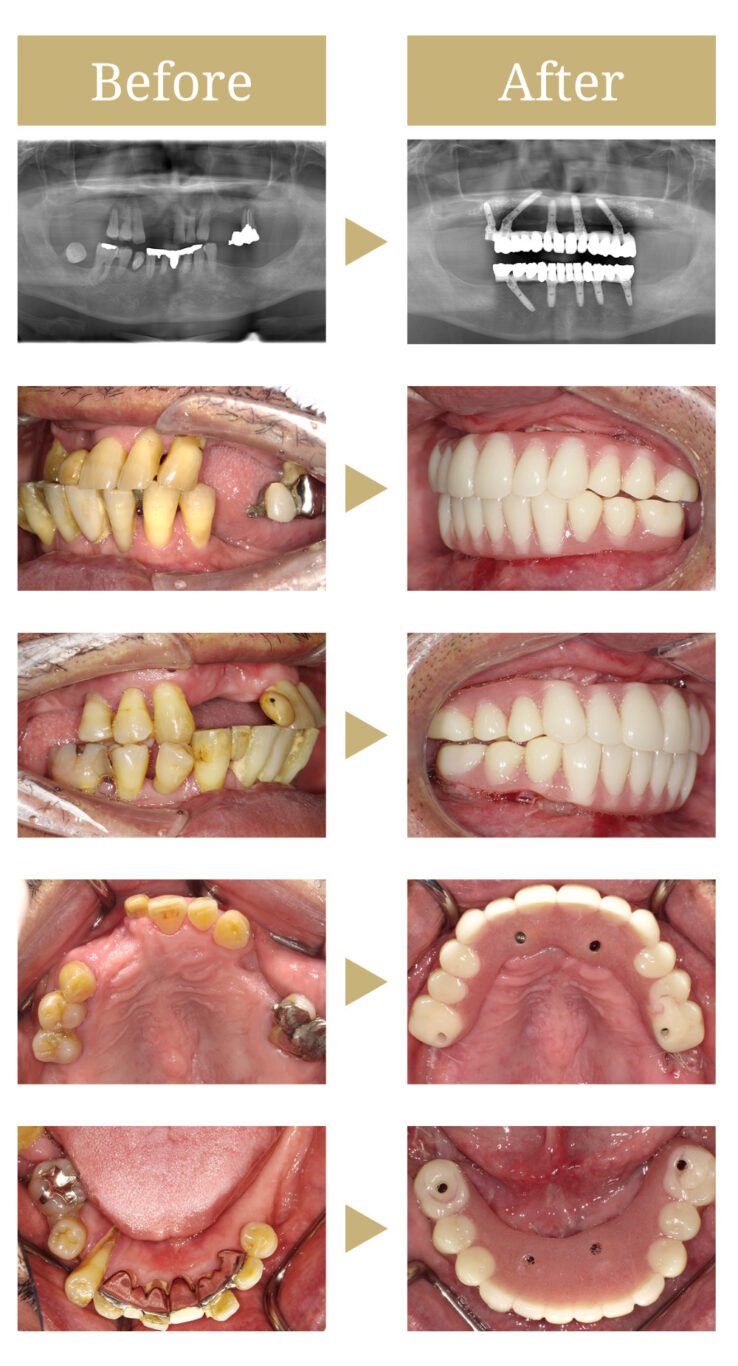

インプラント・オールオン4・抜歯・ジルコニア

全体的に残存歯は状態が悪く、上顎には歯根露出や動揺が強く見られるため、全顎的な治療が必要と判断しました。

上顎は骨が薄く骨造成が必要なためサイナスリフトと呼ばれる術式を併用し、上下Allon4での治療を提案しました。

患者様自身は、口内環境に強く不満を持っており、短期間の治療と早期に見た目を改善したいとの希望に沿って、上下オールオン4を行い、審美面の改善と治療の短縮を図りました。

治療後、咀嚼の問題もなくなり、嚙み合わせも安定しました。